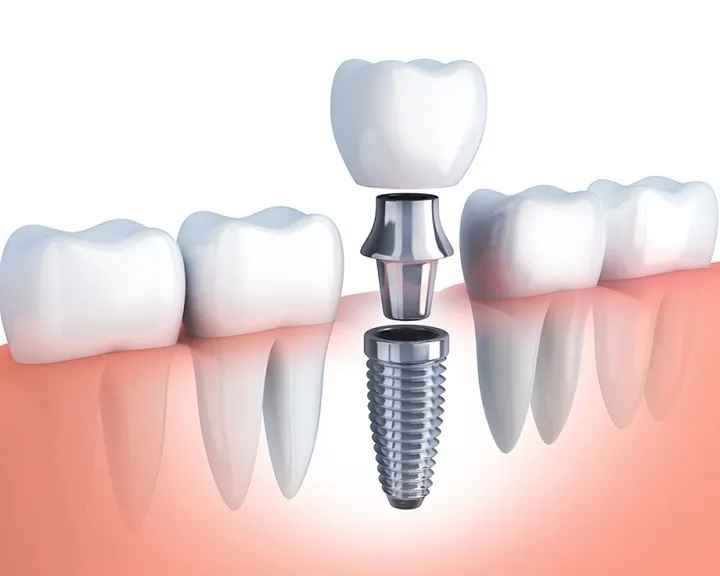

Nhổ răng và phục hình răng cửa khép thưa

Sau khi nhổ răng, nếu thấy khe hở không quá lớn, nha sĩ có thể gợi ý cho bạn sử dụng phương pháp phục hình răng để thu hẹp khoảng trống của răng kẹ vừa nhổ.

Một số phương pháp phổ biến như:

- Bọc răng sứ

- Dán sứ

- Trám răng

Ưu điểm của phương pháp này là nhanh chóng, chỉ mất khoảng 3 – 4 ngày để phục hình răng. Nhưng bạn lưu ý chỉ thực hiện khi kích thước của răng kẹ rất nhỏ, sau khi nhổ để lại một khoảng trống bé xíu, nếu không răng sau khi phục hình sẽ rất to, làm mất cân đối hàm răng.